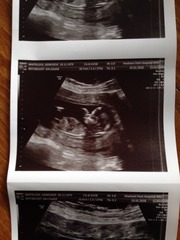

Finally remembered to get my scan pics though, these two were the best

August 2016 (3) - scans fast approaching, teeny tiny bumps appearing, and sickness easing....we hope!

lily yours is so lovely and clear too - what a sweet little profile! hope you're not in hospital too long.

jw and lily, lovely to see your scan pictures, I bet it's all feeling a little more real.

lovely scan pics lily and jw all getting real now!

Lovely pics too lily! Sorry you're still in the hospital, hope you're doing better now.

Lovely scan pics jw and lily, congrats!